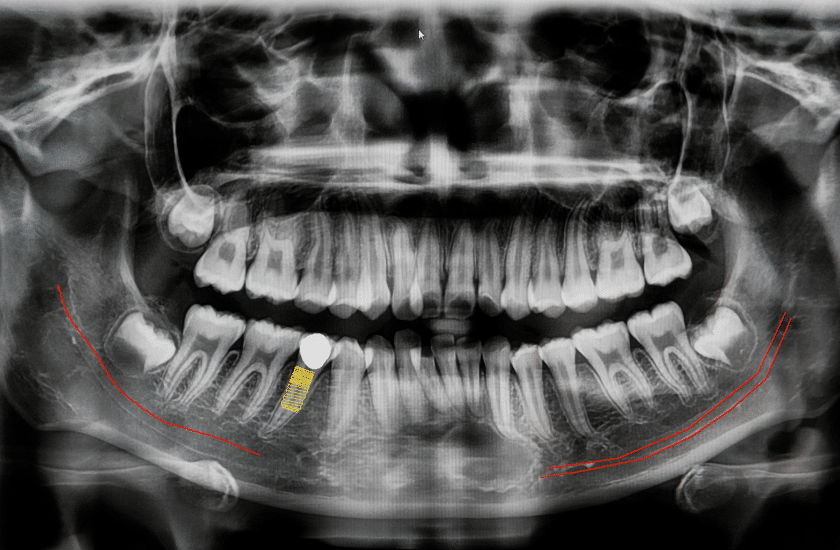

Another benefit of digital x-rays is that they provide more detailed images than film x-rays. This means that your dentist or oral health care provider can more easily identify problems such as tooth decay, gum disease, and infections. Digital x-rays can also be enhanced with special software so that small details can be more clearly seen. Overall, digital x-rays offer a number of advantages over traditional film x-rays. They are safe, emit less radiation, and provide more detailed images. If you are in need of dental imaging, talk to your dentist about whether digital x-rays are right for you.

Digital X-rays work by using a small electronic sensor to capture the image of your teeth and bones. The sensor is then connected to a computer, which creates a digital image of your mouth. This image can be viewed on a monitor in the dental office, and can be stored electronically for future reference.

Digital X-rays offer a number of advantages over traditional film X-rays. First, they emit far less radiation than film X-rays, so they are safer for both patients and dental staff. Second, they produce high-quality images that can be enhanced for better viewing. And third, they are quick and easy to take, which saves time in the dental office.

– Enhanced images: Digital x-ray images can be enhanced using software, making it easier to see small details that might be obscured on a traditional film x-ray.

- The X-ray itself is painless and only takes a few seconds. Afterward, you can expect to see images of your teeth and jaw on a computer screen. These images can be magnified, rotated, and enhanced for better clarity. Your dentist or orthodontist will then use these images to diagnose any problems and develop a treatment plan.